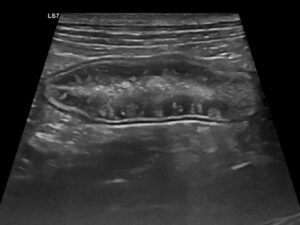

La ecografía abdominal es de gran ayuda, ya que la presencia de engrosamiento de la mucosa intestinal es frecuente en EII y linfoma intestinal difuso, mientras que la aparición de estriaciones hiperecogénicas en la mucosa se relaciona con la presencia de linfangiectasia en más del 90 % de los casos10 (imagen 2).

Imagen 2. A y B) Ecografías de un bulldog francés de 8 años con signos clínicos compatibles con EPP, en las que se aprecian estriaciones hiperecogénicas en la mucosa, que en la mayoría de los casos se corresponden con linfangiectasias, que posteriormente se confirmaron mediante histopatología. C) Ecografía de una perra mestiza con hipoalbuminemia grave asociada a una enteropatía inflamatoria. Puede apreciarse una hiperecogenicidad marcada y difusa de la mucosa intestinal, así como la presencia de efusión abdominal.